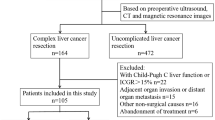

Between July 2006 and September 2013, a total of 288 patients underwent liver resection at the University of Tsukuba Hospital. Of these patients, 48 who underwent liver resection and another surgery simultaneously were excluded. The remaining 240 patients were analyzed. These patients included 168 males and 72 females with a median age of 65 years (range 17–81 years). Patients were sequentially divided into two groups: those without 3D preoperative simulation (without 3D group, n = 120) and those with 3D preoperative simulation (3D group, n = 120) (Fig. 1). Before 2010 (and thus prior to the adoption of the 3D simulation system), 120 sequential patients underwent a hepatectomy without preoperative 3D simulation (Table 1). These patients included 79 men and 41 women with a median age of 65 years (range 22–80 years). The preoperative diagnoses for these patients were as follows: 59 diagnosis of hepatocellular carcinoma (HCC), 3 of intrahepatic cholangiocarcinoma (ICC), 10 of extrahepatic cholangiocarcinoma, 29 of metastatic liver tumors, 7 of donor for liver transplantation, and 9 of other. The patients were classified according to the Child–Pugh classification as grade A (n = 111), grade B (n = 8) or grade C (n = 1). One case received preoperative portal vein embolization (PVE) to enlarge the remnant liver volume. Twenty-nine patients had a history of hepatectomy. The surgical procedure performed depended on the location of the primary tumor and liver function. Ten patients underwent extended left hepatectomy. Five patients underwent extended right hepatectomy. Fourteen patients underwent left hepatectomy. Four patients were subjected to right hepatectomy. Twenty-one patients were subjected to sectionectomy. Twenty patients underwent segmentectomy, and 46 patients underwent partial resection. The characteristics of the 120 patients for whom preoperative simulation was performed are detailed in Table 1. These 120 patients consisted of 89 men and 31 women with a median age of 67 years (range 17–81 years). Of these patients, 62 were preoperatively diagnosed with HCC, 15 with ICC, 10 with extrahepatic cholangiocarcinoma, 24 with metastatic liver tumors, 3 as a transplantation donor, and 6 with other. The patients were classified according to the Child–Pugh classification as grade A (n = 115), grade B (n = 4) or grade C (n = 1). Four cases received preoperative PVE. Nine patients had a history of hepatectomy. Fourteen patients underwent extended left hepatectomy. Seven patients were subjected to extended right hepatectomy. Eleven patients underwent left hepatectomy, whereas three underwent right hepatectomy. Twenty-four patients underwent sectionectomy, and 12 underwent segmentectomy. Forty-nine patients experienced partial resection. There were no significant differences in characteristics other than the length of the surgeon’s career between the without 3D group and the 3D group.

Flowchart of the study. Of the 288 consecutive patients who underwent liver resection, 48 patients who had received a simultaneous surgery were excluded. The remaining 240 patients were divided into two groups: before adoption of 3D preoperative simulation (the without 3D group) or after adoption of 3D preoperative simulation (the 3D group)